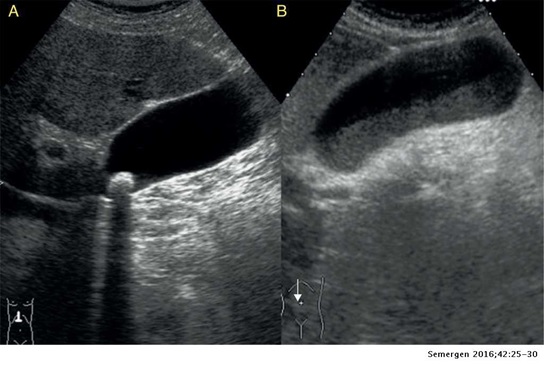

Ecotomografía Abdominal. Es el examen de elección para el estudio inicial de un paciente con sospecha de colecistitis aguda, ya que es un examen no invasivo, de bajo costo, alta disponibilidad, alta sensibilidad y especificidad. Corte longitudinal en el hipocondrio derecho:

- A: colelitiasis, imagen intravesicular hiperecogénica con sombra posterior a nivel del cuello.

- B: barro biliar, ocupación de la porción más declive de la vesícula con material ecogénico y con nivel horizontal.